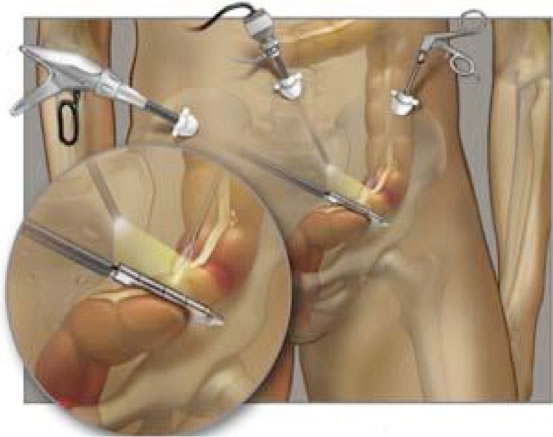

Δύο είναι οι βασικές προσπελάσεις για τη χειρουργική εκτομή του παχέος εντέρου, η οποία όταν αφορά το κόλον λέγεται κολεκτομή:

Λαπαροσκοπική προσπέλαση: Χρησιμοποιείται το λαπαροσκόπιο, το οποίο είναι ένας λεπτός ενδοσκοπικός σωλήνας, ο οποίος συνδέεται με μία πηγή φωτός και μία βίντεο-κάμερα. Ο χειρουργός βλέπει όλα τα όργανα της κοιλιάς με τη βοήθεια του λαπαροσκοπίου, χωρίς να χρειάζεται να «ανοίξει» την κοιλιά. Τρεις ή τέσσερις μικρές οπές γίνονται πάνω στην κοιλιά και μέσα από αυτές τοποθετούνται ειδικά, λεπτά χειρουργικά εργαλεία, τα οποία χρησιμοποιούνται για να απελευθερώσουν το παχύ έντερο από τις φυσικές προσφύσεις του και ταυτόχρονα για να αποκόψουν την αιμάτωσή του από τα τροφοφόρα αγγεία του και να καθαρίσουν τους λεμφαδένες που βρίσκονται στο λίπος που περιβάλει το παχύ έντερο. Το χειρουργικό παρασκεύασμα αφαιρείται μέσα από μία μικρή τομή που γίνεται στην κοιλιά. Έτσι ο ασθενής αποφεύγει το σημαντικό stress του «ανοικτού» χειρουργείου, νοιώθει καλύτερα μετά το χειρουργείο, αναρρώνει πιο γρήγορα, με λιγότερο πόνο και δυσφορία και επιστρέφει στο σπίτι του και στις καθημερινές ασχολίες του ταχύτερα.

Η λαπαροσκοπική προσπέλαση για τη χειρουργική αντιμετώπιση του καρκίνου του παχέος εντέρου είναι ογκολογικά ισοδύναμη με την «ανοικτή» προσπέλαση

Πέρα όμως από την καλύτερη ανάρρωση που προσφέρει η λαπαροσκοπική χειρουργική, τα ογκολογικά αποτελέσματα δεν διαφέρουν από την «ανοικτή» χειρουργική, με άλλα λόγια, για να έχει ο ασθενής την πιο ανεπίπλεκτη και μακρότερη επιβίωση, αυτό που έχει τη μεγαλύτερη σημασία είναι ο άρτιος, ριζικός χειρουργικός καθαρισμός που πρέπει να διενεργήσει ο ειδικός χειρουργός, ανεξαρτήτου της προσπέλασης, λαπαροσκοπικής ή «ανοικτής» που θα χρησιμοποιήσει. Για αυτό τα καλύτερα αποτελέσματα στη θεραπεία του καρκίνου του παχέος εντέρου τα πετυχαίνουν οι εξειδικευμένοι χειρουργοί παχέος εντέρου, οι οποίοι εξάλλου έχουν εκπαιδευτεί στις ελάχιστα επεμβατικές χειρουργικές τεχνικές και χρησιμοποιούν ως επί το πλείστον τη λαπαροσκοπική προσπέλαση, και όχι οι χειρουργοί με εμπειρία γενικά στη λαπαροσκοπική χειρουργική, αλλά χωρίς εξεδίκευση και βαθιά γνώση της χειρουργικής του παχέος εντέρου.

«Ανοικτή» προσπέλαση: Ο χειρουργός εκτελεί μία μεγάλη τομή στην κοιλιά προκειμένου να αφαιρέσει το προσβεβλημένο από τον καρκίνο τμήμα του παχέος εντέρου μαζί με τους λεμφαδένες της περιοχής. Στο 20% των περιπτώσεων η επέμβαση για τον καρκίνο του παχέος εντέρου δεν μπορεί να ολοκληρωθεί λαπαροσκοπικά, οπότε ο χειρουργός πρέπει να «μετατρέψει» την επέμβαση σε «ανοικτή». Τόσο η λαπαροσκοπική όσο και η «ανοικτή» κολεκτομή διενεργούνται με γενική αναισθησία και ο ασθενής χρειάζεται νοσηλεία 4-7 ημερών, αναλόγως της περίπτωσης. Αρκετές μεγάλες διεθνείς μελέτες έχουν ήδη επιβεβαιώσει ότι τόσο η λαπαροσκοπική όσο και η «ανοικτή» προσπέλαση στη χειρουργική αντιμετώπιση του καρκίνου του παχέος εντέρου είναι ογκολογικά ισοδύναμες και προσφέρουν εφάμιλλα αποτελέσματα όσον αφορά την τελική μακροπρόθεσμη έκβαση των ασθενών, εφόσον εκτελούνται από εξειδικευμένους χειρουργούς παχέος εντέρου.

Ο χειρουργός σας είναι υποχρεωμένος να σας εξηγήσει με ακρίβεια και ειλικρίνεια τα πλεονεκτήματα και τα μειονεκτήματα της «ανοικτής» και της λαπαροσκοπικής κολεκτομής, ανεξαρτήτου των επαγγελματικών και οικονομικών οφελών που προσφέρει η εφαρμογή της σύγχρονης τεχνολογίας της λαπαροσκοπικής χειρουργικής.